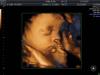

Девчат скиньте свои 3д снимки в 28 недель, у кого есть. Думаю получится ли сделать хороший кадр или дать еще малышу подрасти

Жуть такая на самом деле эти фотки 😅 но я тоже собираюсь 😂 врач сказал в 28 самый идеальный срок, уж не знаю даже, потому что девчонки все по разному говорят